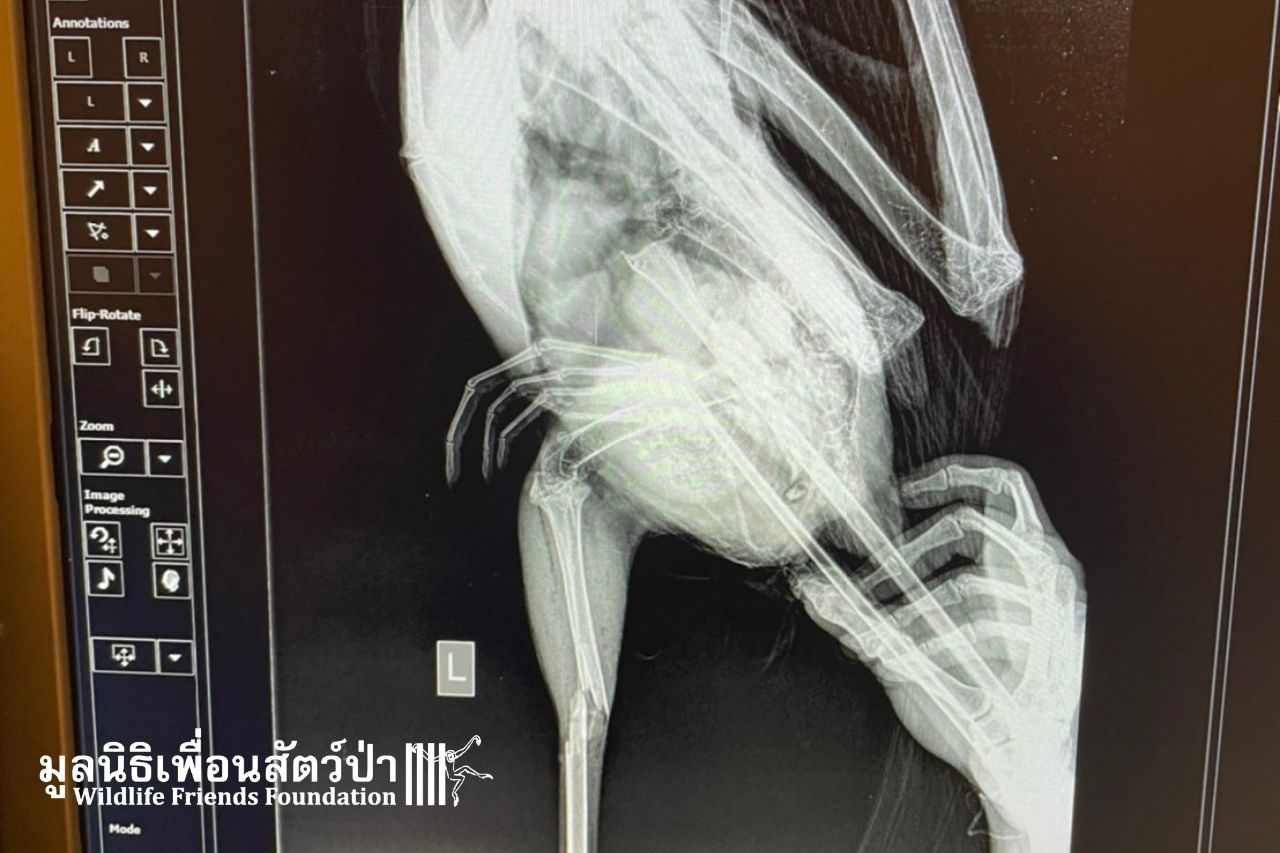

We suspect from the injuries that this Painted Stork was hit by a car or experienced some other kind of impact trauma. The stork was found at a restaurant where the people there, kindly, kept it safe and tried to provide some first aid.

The stork has a broken leg and will likely need surgery to pin the bones together. Otherwise, there is no hope of the stork getting back to the wild. It is only with your generosity that we can be there for wild animals in urgent need. Any donation, big or small, can help this beautiful Painted Stork.